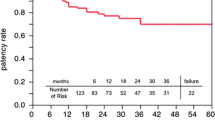

Amin S, Pinho-Gomes AC, Taggart DP. Relationship of Intraoperative transit time Flowmetry findings to angiographic graft patency at follow-up. Ann Thorac Surg. 2016;101(5):1996–2006.

Lehnert P, et al. Transit-time flow measurement as a predictor of coronary bypass graft failure at one year angiographic follow-up. J Card Surg. 2015;30(1):47–52.